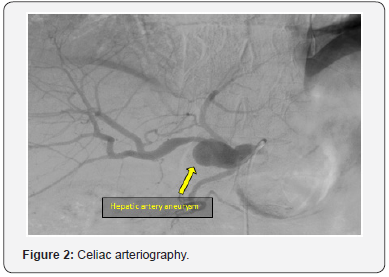

A 66-year-old man was admitted in our department with a hepatic artery aneurysm. The aneurysm was asymptomatic and was an incidental finding as a result of an abdominal ultrasound to investigate an episode of pain in the umbilical region. Comorbidities in our patient included hyperlipidaemia and hypertension. The patient had no history of abdominal trauma or invasive hepatobiliary procedures. A computed tomography angiography (CTA) was performed and revealed a 26mm diameter saccular aneurysm in the common hepatic artery at the level of the origin of the gastroduodenal artery (Figure 1). An angiography of the celiac trunk was also performed for better anatomical characterization (Figure 2). Our initial plan was to perform a bypass from the splenic artery to the proper hepatic artery, but intraoperatively we verified that this segment was also aneurysmatic. The dissection of the aneurysm which, presented inflammatory characteristics, was very laborious and we did not identify any healthy segment of the proper hepatic artery. We performed ligation of the origin of the common hepatic artery and of the proper hepatic artery to exclude the aneurysm with subsequent interposition of reversed great saphenous vein graft between the splenic artery and the right hepatic artery.